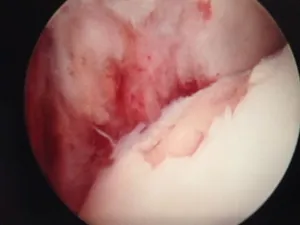

A series of intraop ankle arthroscopy pics of synovial chondromatosis with OCD talus and tibia and microfracture.

Pic after microfracture and debridement of above OCD.

Pic during microfracture of tibial OCD.